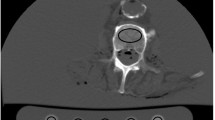

To derive BMD measurements from original as well as virtual low-dose and sparse-sampled MDCT scans with FBP or SIR, regions of interest (ROIs) were placed in the femoral neck of the left and right sides of each subject. First, axial images of the dataset with 100% of the tube current and 100% of the projections (D100 P100), using FBP as the clinical standard of reference, were opened using ImageJ (https://imagej.nih.gov/ij/) [31, 32]. Then, we identified the axial slice in which the neck was visualized best and drew a quadrangular ROI in this section, including the cortical and trabecular bone compartments (Fig. 1). The same placement strategy and shape of the ROI have been used in a previous study of our group [9]. The two ROIs (femoral neck of both sides) were saved for each subject, and the individual ROIs in the used image stack (D100 P100 with FBP) were then transferred (as intrinsically co-registered) to the other datasets containing the virtual low-dose (D50 P100, D25 P100, and D10 P100) and sparse-sampled imaging data (D100 P50, D100 P25, and D100 P10) of the respective subject, considering both FBP and SIR. We then extracted mean HU from these ROIs, which were subsequently converted into volumetric BMD values (in g/cm3) using the information of the reference phantom [9, 13]. The BMD values of the left and right sides were averaged in each subject.

Placement of regions of interest (ROIs). This figure illustrates the placement of a ROI in the femoral neck in a representative case using axial slices derived from full-dose multi-detector computed tomography (MDCT) using filtered back projection (FBP). The ROI was quadrangular and included the cortex. ROIs were not placed in areas with circumscribed lucencies (e.g., cystic lesions) or sclerosis (e.g., bone islands). The placement of the ROI at the other side’s femoral neck was conducted in an analogous way